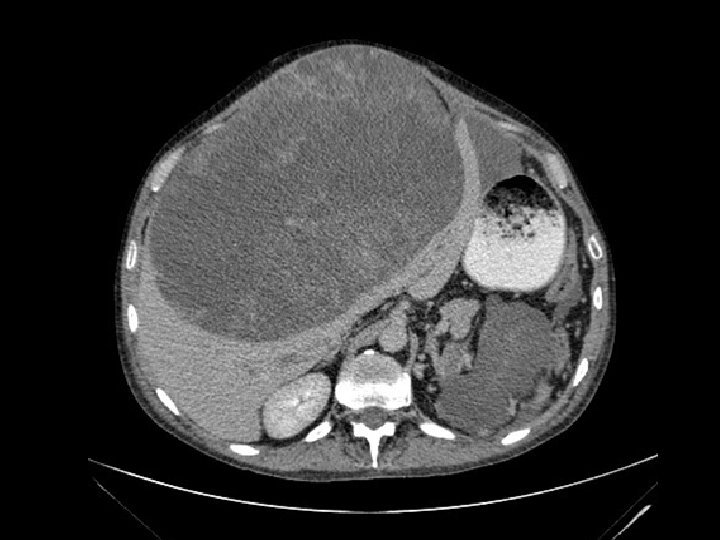

¿Qué es un paciente con TG de mal pronóstico? Un paciente con un TG de mal pronóstico es aquel que tiene una probabilidad de curación del 50% o menos…. Que en un tumor en primera línea sería. .

Definición Un paciente con un TG de mal pronóstico es aquel que tiene una probabilidad de curación del 50% o menos…. Que en un tumor en segunda línea sería. . .